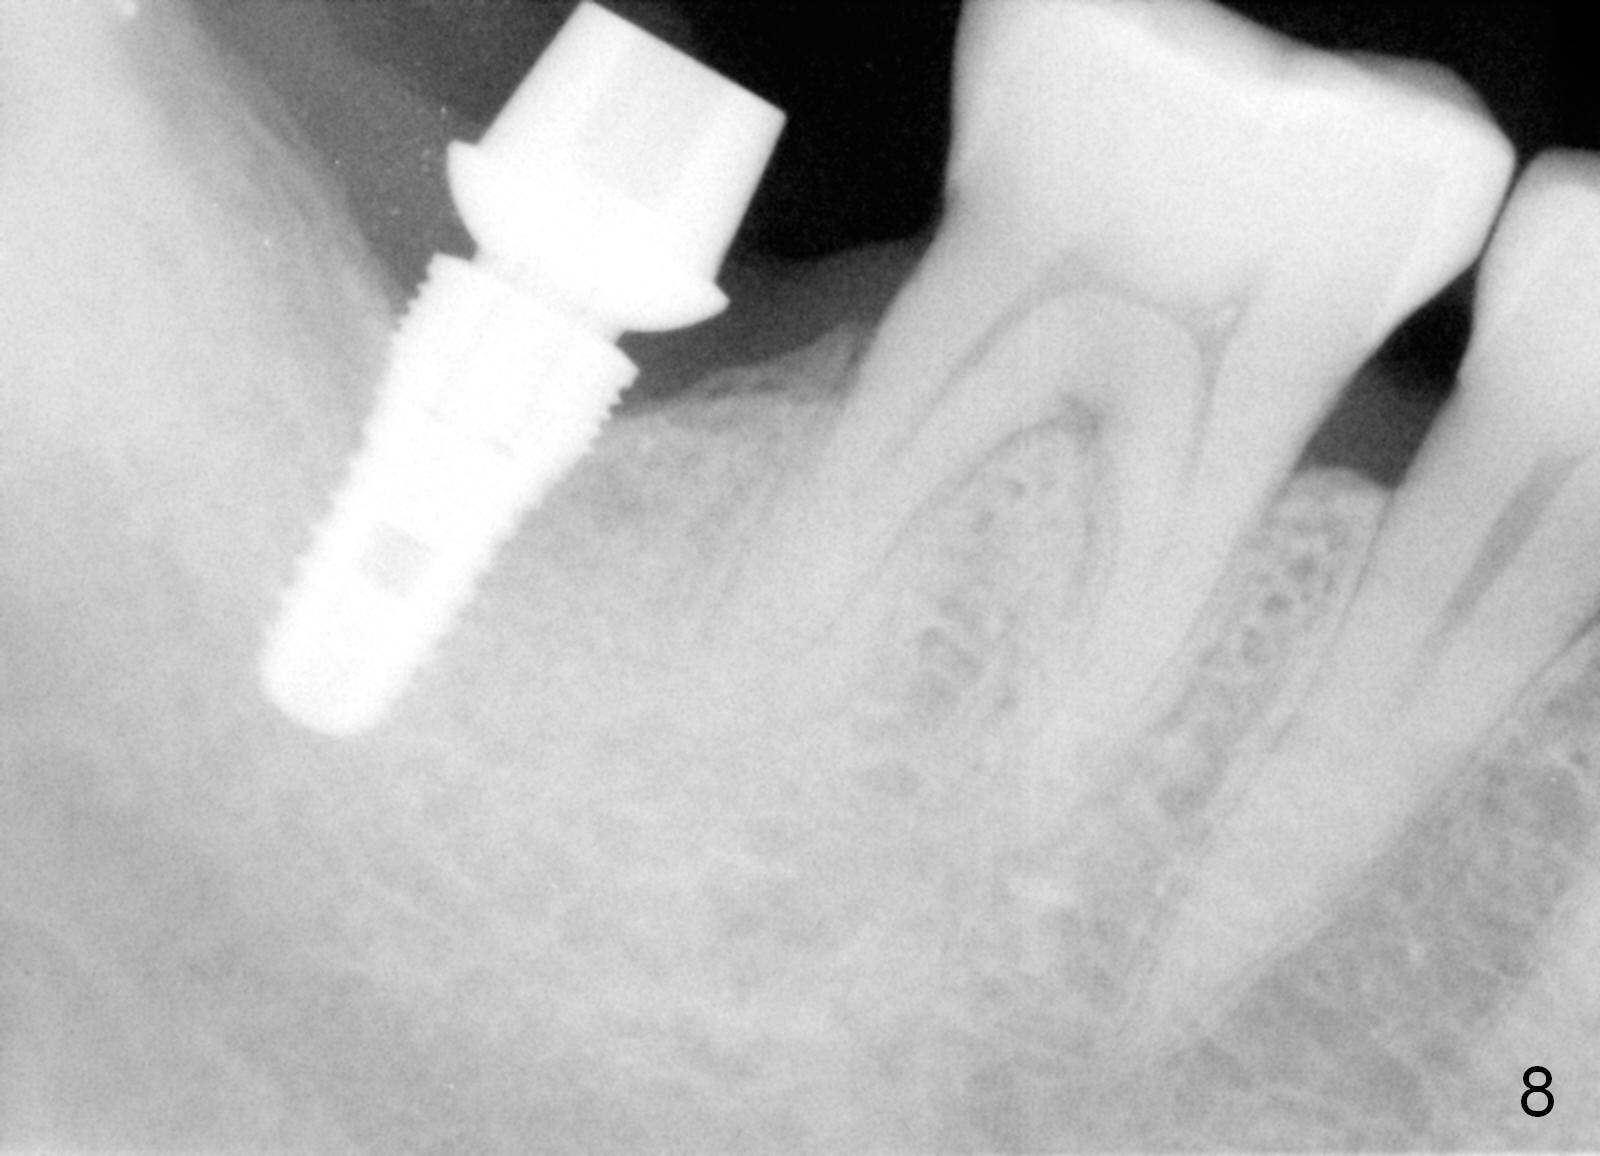

The bone feels to have relatively low density during osteotomy. The final osteotomy drill is 4.5x10 mm; a 5x10 mm implant is placed (under prep) with insertion torque >56 Ncm (Fig.6 I). A 6.8x4(2) mm cemented abutment (A) is placed immediately for an immediate provisional. The latter is opposed to the immediate provisional at #2.

The gingiva heals around the provisional 20 days postop when the patient returns for provisional reline and recementation (Fig.7 P). Note that the margin of the provisional is lower than that of the neighboring teeth, indicating bone loss due to delayed implant placement.